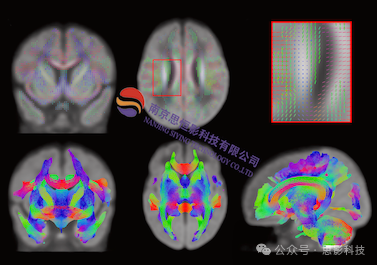

近年来,扩散磁共振成像(dMRI)领域在成像技术、数据处理方法上都取得了重要进展。相对于传统的扩散张量成像(DTI),高角分辨率扩散成像HARDI很好地解决了纤维交叉问题,而神经突方向分散度和密度成像(NODDI)对白质微结构异常具有更高的特异性,对神经元细胞内外组织及脑脊液有更好的区分度,在大脑发育及老化、脑血管病变、脑神经损伤等方面的研究取得了诸多成果。约束球形反卷积(CSD)与弥散频谱成像(DSI)可以更精确地追踪具有复杂走形的纤维束,有效地弥补了DTI的不足,已成为脑连接组研究和临床疾病探索的潜力技术。扩散成像序列的数据处理方法近年来也有一些革新,比如基于Fixel的分析方法,可以估计纤维束密度、纤维束横截面面积等指标,这些技术革新为研究人员提供了新的研究思路和视野,相关高质量的研究成果也层出不穷。

内容主要包括:工作环境的准备(虚拟机、Linux系统基础知识等);基础与进阶版预处理;高角分辨率扩散磁共振成像(HARDI);扩散峰度成像(DKI);神经突方向分散度和密度成像(NODDI);Constrained Spherical Deconvolution(csd)与弥散频谱成像(DSI)方法,;基于CSD与DSI的脑网络构建与指标计算;基于Fixel的数据分析(纤维束密度及横截面积计算);